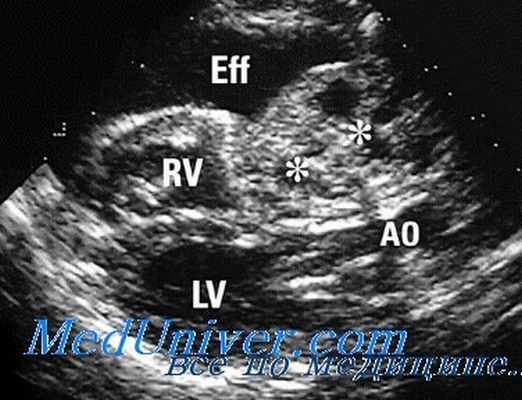

- состояние внешней оболочки, перикарда.

- болезни перикарда; .

Эхокардиография позволяет получать ряд количественных показателей, характеризующих основную функцию сердца — сократительную. Уже на ранних этапах снижения этой функции можно распознать эти нарушения и проводить соответствующее лечение. Повторные исследования позволяют врачу оценивать эффективность лечебных мероприятий. Эхокардиография позволяет с большой точностью распознавать заболевания наружной оболочки сердца — перикарда, хорошо виды утолщения листков перикарда, спайки между ними, наличие жидкости в полости перикарда. Четко выявляются опухоли сердца. Исследование периферических сосудов выявляет, главным образом, сужение их просвета.

- перикардиальной патологии — наличия жидкости в околосердечной сумке; с помощью эхокардиографии (под ее контролем) можно безопасно удалить перикардиальную жидкость при тампонаде сердца;